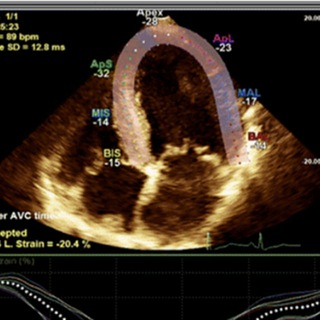

Марафон ЭХОКГ для кардиологов

СТАРТ 1 августа. Будем учиться анализировать протоколы УЗИ сердца.